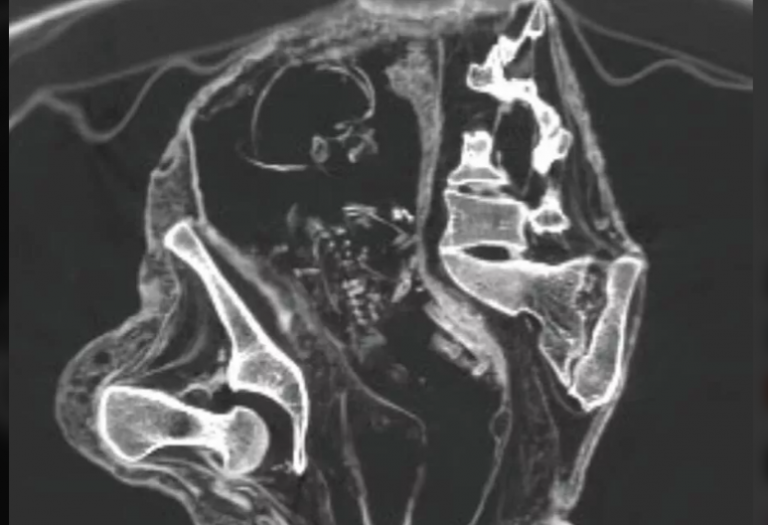

Результаты томографии оказались, мягко говоря, удивительными. В утробе мумии были обнаружены кости плода. На снимках четко видно, что он лежит на спине, головой вниз, а его руки расположены ближе к тазовой области. Такое положение характерно для поздних сроков беременности, что указывает на то, что Монтсеррат умерла примерно за несколько месяцев до несостоявшихся родов. Доктор Хосе Зальса, один из ведущих экспертов, отметил, что это уникальная находка. Подобные случаи крайне редки в археологии, особенно учитывая возраст мумии и состояние сохранности останков.

Особенности плода

Еще один удивительный факт, обнаруженный учеными, касается анатомических особенностей плода. Единственным сходством между матерью и ребенком, которое удалось зафиксировать на данный момент, является наличие конечностей с тремя пальцами. Это необычное строение остается загадкой для исследователей. Для более точного определения происхождения плода и его возможной связи с матерью в ближайшее время планируется провести анализ ДНК.